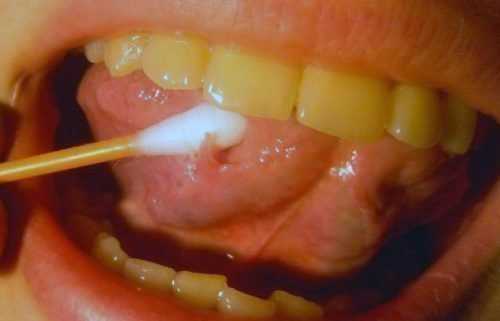

ΠΠ°Π½Π΄ΠΈΠ΄ΠΎΠ·ΠΡΠΎ Π³ΡΠΈΠ±ΠΊΠΎΠ²ΠΎΠ΅ Π·Π°Π±ΠΎΠ»Π΅Π²Π°Π½ΠΈΠ΅, ΠΊΠΎΡΠΎΡΠΎΠ΅ Ρ Π°ΡΠ°ΠΊΡΠ΅ΡΠΈΠ·ΡΠ΅ΡΡΡ ΠΎΠ±ΡΠ°Π·ΠΎΠ²Π°Π½ΠΈΠ΅ΠΌ Π±Π΅Π»ΠΎΠ³ΠΎ ΡΠ²ΠΎΡΠΎΠΆΠΈΡΡΠΎΠ³ΠΎ Π½Π°Π»Π΅ΡΠ° Π² ΡΠΎΡΠΎΠ²ΠΎΠΉ ΠΏΠΎΠ»ΠΎΡΡΠΈ. ΠΠΎΠ·Π±ΡΠ΄ΠΈΡΠ΅Π»Π΅ΠΌ ΠΌΠΎΠ»ΠΎΡΠ½ΠΈΡΡ ΡΠ²Π»ΡΡΡΡΡ Π³ΡΠΈΠ±ΠΊΠΈ ΡΠΎΠ΄Π° ΠΠ°Π½Π΄ΠΈΠ΄Π°, ΡΡΠΈ ΠΏΡΠΎΡΡΠ΅ΠΉΡΠΈΠ΅ ΠΌΠΈΠΊΡΠΎΠΎΡΠ³Π°Π½ΠΈΠ·ΠΌΡ ΠΎΡΠ½ΠΎΡΡΡΡΡ ΠΊ ΡΡΠ»ΠΎΠ²Π½ΠΎ-ΠΏΠ°ΡΠΎΠ³Π΅Π½Π½ΠΎΠΉ ΠΌΠΈΠΊΡΠΎΡΠ»ΠΎΡΠ΅ ΡΠ»ΠΈΠ·ΠΈΡΡΡΡ ΠΈ Π² Π½ΠΎΡΠΌΠ΅ Π½Π΅ Π²ΡΠ·ΡΠ²Π°ΡΡ ΠΏΠΎΠ²ΡΠ΅ΠΆΠ΄Π΅Π½ΠΈΡ ΠΌΡΠ³ΠΊΠΈΡ ΡΠΊΠ°Π½Π΅ΠΉ.

ΠΡΠΈ ΠΊΠ°Π½Π΄ΠΈΠ΄ΠΎΠ·Π½ΠΎΠΌ ΡΡΠΎΠΌΠ°ΡΠΈΡΠ΅ Π½Π° ΡΠ·ΡΠΊΠ΅ ΠΈ ΡΠ»ΠΈΠ·ΠΈΡΡΡΡ ΠΎΠ±ΠΎΠ»ΠΎΡΠΊΠ°Ρ ΠΎΠ±ΡΠ°Π·ΡΡΡΡΡ Π±Π΅Π»ΡΠ΅ ΠΏΡΡΠ½Π°, ΠΏΠΎΠΊΡΡΡΡΠ΅ Π½Π°Π»Π΅ΡΠΎΠΌ. ΠΠ³ΠΎ ΠΊΠΎΠ½ΡΠΈΡΡΠ΅Π½ΡΠΈΡ Π½Π°ΠΏΠΎΠΌΠΈΠ½Π°Π΅Ρ ΡΠ²Π΅ΡΠ½ΡΠ²ΡΠ΅Π΅ΡΡ ΠΌΠΎΠ»ΠΎΠΊΠΎ. ΠΠ°ΠΊΡΠ΅ΡΠΈΠ°Π»ΡΠ½ΡΠ΅ ΠΎΡΠ»ΠΎΠΆΠ΅Π½ΠΈΡ Π»Π΅Π³ΠΊΠΎ ΡΠ½ΠΈΠΌΠ°ΡΡΡΡ, Π½Π° ΠΈΡ ΠΌΠ΅ΡΡΠ΅ ΠΎΡΡΠ°ΡΡΡΡ ΠΊΡΠΎΠ²ΠΎΡΠΎΡΠ°ΡΠΈΠ΅ ΡΠ·Π²ΠΎΡΠΊΠΈ. ΠΠΎΠ»ΡΠ½ΡΠ΅ ΠΆΠ°Π»ΡΡΡΡΡ Π½Π° Π½Π΅ΠΏΡΠΈΡΡΠ½ΡΠΉ ΠΌΠ΅ΡΠ°Π»Π»ΠΈΡΠ΅ΡΠΊΠΈΠΉ ΠΏΡΠΈΠ²ΠΊΡΡ Π²ΠΎ ΡΡΡ, Π±ΠΎΠ»Ρ, ΠΆΠΆΠ΅Π½ΠΈΠ΅ ΠΏΡΠΈ ΡΠΏΠΎΡΡΠ΅Π±Π»Π΅Π½ΠΈΠΈ ΠΏΠΈΡΠΈ. ΠΡΠΈ Ρ ΡΠΎΠ½ΠΈΡΠ΅ΡΠΊΠΎΠΌ ΡΠ΅ΡΠ΅Π½ΠΈΠΈ ΡΡΠΎΠΌΠ°ΡΠΈΡΠ° Π³ΡΠΈΠ±ΠΊΠΎΠ²Π°Ρ ΠΈΠ½ΡΠ΅ΠΊΡΠΈΡ ΠΏΡΠΎΠ½ΠΈΠΊΠ°Π΅Ρ Π² Π³ΠΎΡΡΠ°Π½Ρ, ΠΌΠΎΠΆΠ΅Ρ ΠΏΠΎΡΠ°ΠΆΠ°ΡΡ Π΄ΡΡ Π°ΡΠ΅Π»ΡΠ½ΡΠ΅ ΠΏΡΡΠΈ, ΠΏΠΈΡΠ΅Π²Π°ΡΠΈΡΠ΅Π»ΡΠ½ΡΠΉ ΡΡΠ°ΠΊΡ, ΠΌΠΎΡΠ΅ΠΏΠΎΠ»ΠΎΠ²ΡΡ ΡΠΈΡΡΠ΅ΠΌΡ.

- ΠΠ°Π½Π΄ΠΈΠ΄ΠΎΠ·Π½ΡΠΉ (Π³ΡΠΈΠ±ΠΊΠΎΠ²ΡΠΉ) ΡΡΠΎΠΌΠ°ΡΠΈΡ. ΠΠ·-Π·Π° Π³Π½ΠΎΠΉΠ½ΠΈΡΠΊΠΎΠ² Π±Π΅Π»ΠΎΠ³ΠΎ ΡΠ²Π΅ΡΠ° Π΅Π³ΠΎ Π΅ΡΠ΅ Π½Π°Π·ΡΠ²Π°ΡΡ ΠΌΠΎΠ»ΠΎΡΠ½ΠΈΡΠ΅ΠΉ. ΠΠ΅Π»ΡΠΉ Π½Π°Π»Π΅Ρ ΠΏΠΎΠΊΡΡΠ²Π°Π΅Ρ Π²ΡΡ ΡΠ»ΠΈΠ·ΠΈΡΡΡΡ ΡΠΎΡΠΎΠ²ΠΎΠΉ ΠΏΠΎΠ»ΠΎΡΡΠΈ ΠΈ ΡΠ·ΡΠΊ. ΠΠ°Π±ΠΎΠ»Π΅Π²Π°Π½ΠΈΠ΅ΠΌ ΡΠ°ΡΠ΅ ΡΡΡΠ°Π΄Π°ΡΡ ΠΌΠ°Π»Π΅Π½ΡΠΊΠΈΠ΅ Π΄Π΅ΡΠΈ, Π½ΠΎ ΠΈΠΌ Π±ΠΎΠ»Π΅ΡΡ ΠΈ Π²Π·ΡΠΎΡΠ»ΡΠ΅.